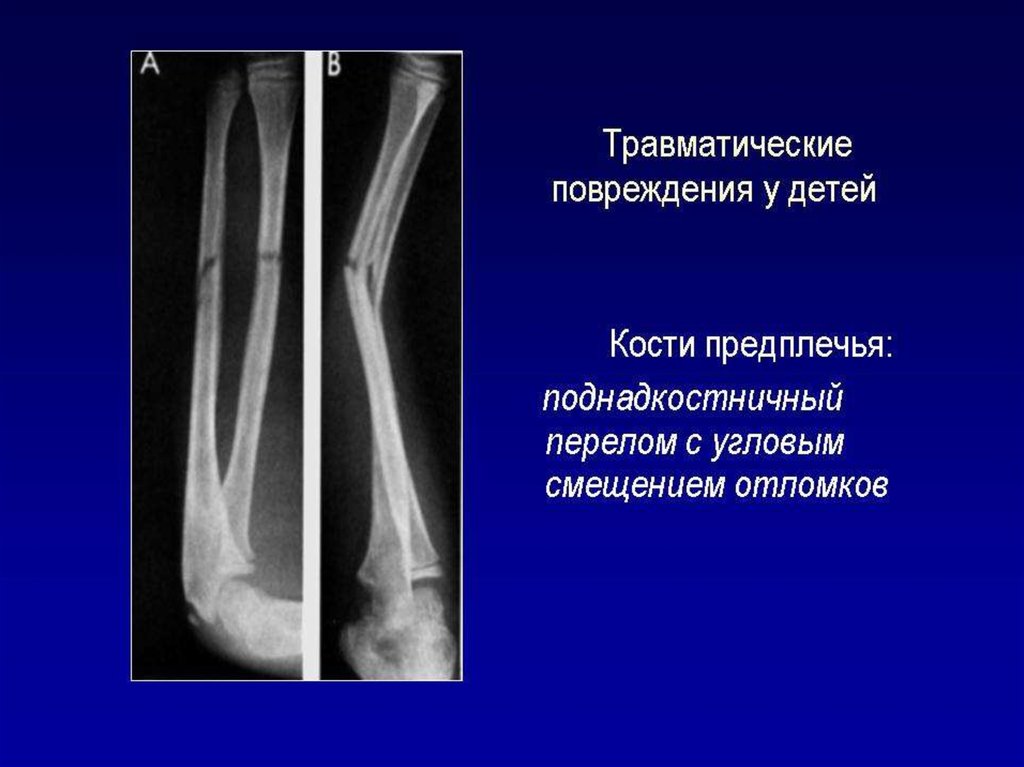

Лучевое исследование костно-суставной системы. Методы исследования. Семиотика